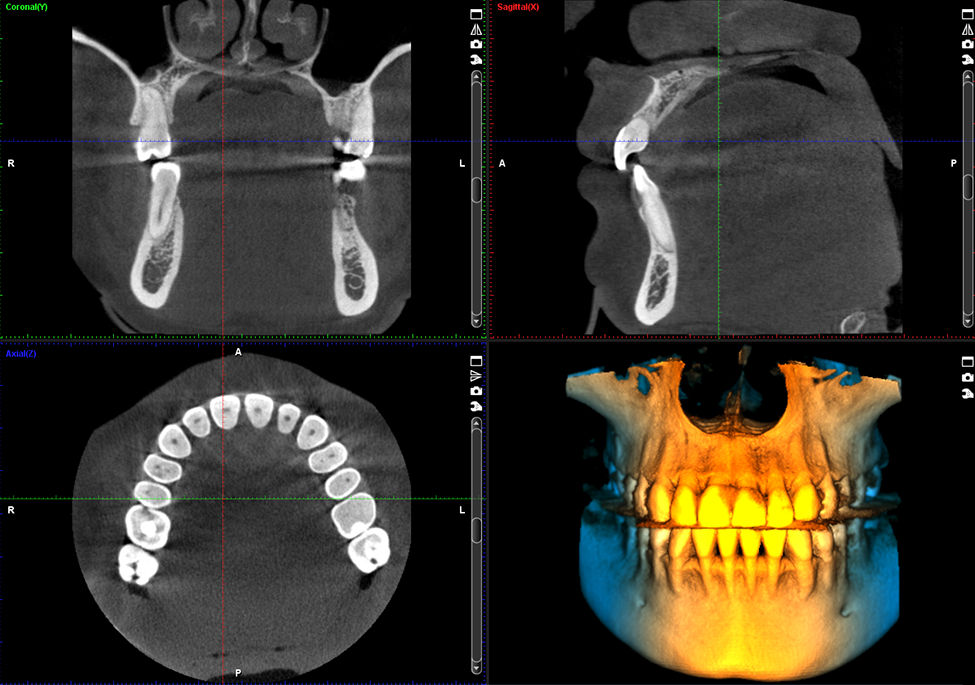

Chất lượng hình ảnh là một trong những yếu tố quan trọng nhất cần xem xét khi lựa chọn một thiết bị 3D. Tất cả các thiết bị của Planmeca đều cung cấp chất lượng hình ảnh tuyệt vời khi sử dụng giao thức hình ảnh Planmeca Ultra Low Dose ™. Nhưng đừng vội tin chúng tôi – bạn có thể tự mình kiểm định chất lượng từ những hình ảnh 3D bên dưới.

Tuy nhiên, cần phân biệt giữa một phim có giá trị chẩn đoán cao với một “phim đẹp”. Có giá trị chẩn đoán cao là phim cung cấp được cho bác sĩ lâm sàng nhiều thông tin từ một bức phim, có thể thấy được những chi tiết nhỏ nhất cho mục đích phát hiện các vấn đề ý nghĩa cho bệnh nhân. Sơ suất trong hiển thị phim có thể dẫn đến những chẩn đoán thiếu chính xác hoặc lập kế hoạch sai. Vì vậy cả việc chụp và hiển thị hình ảnh phim cũng